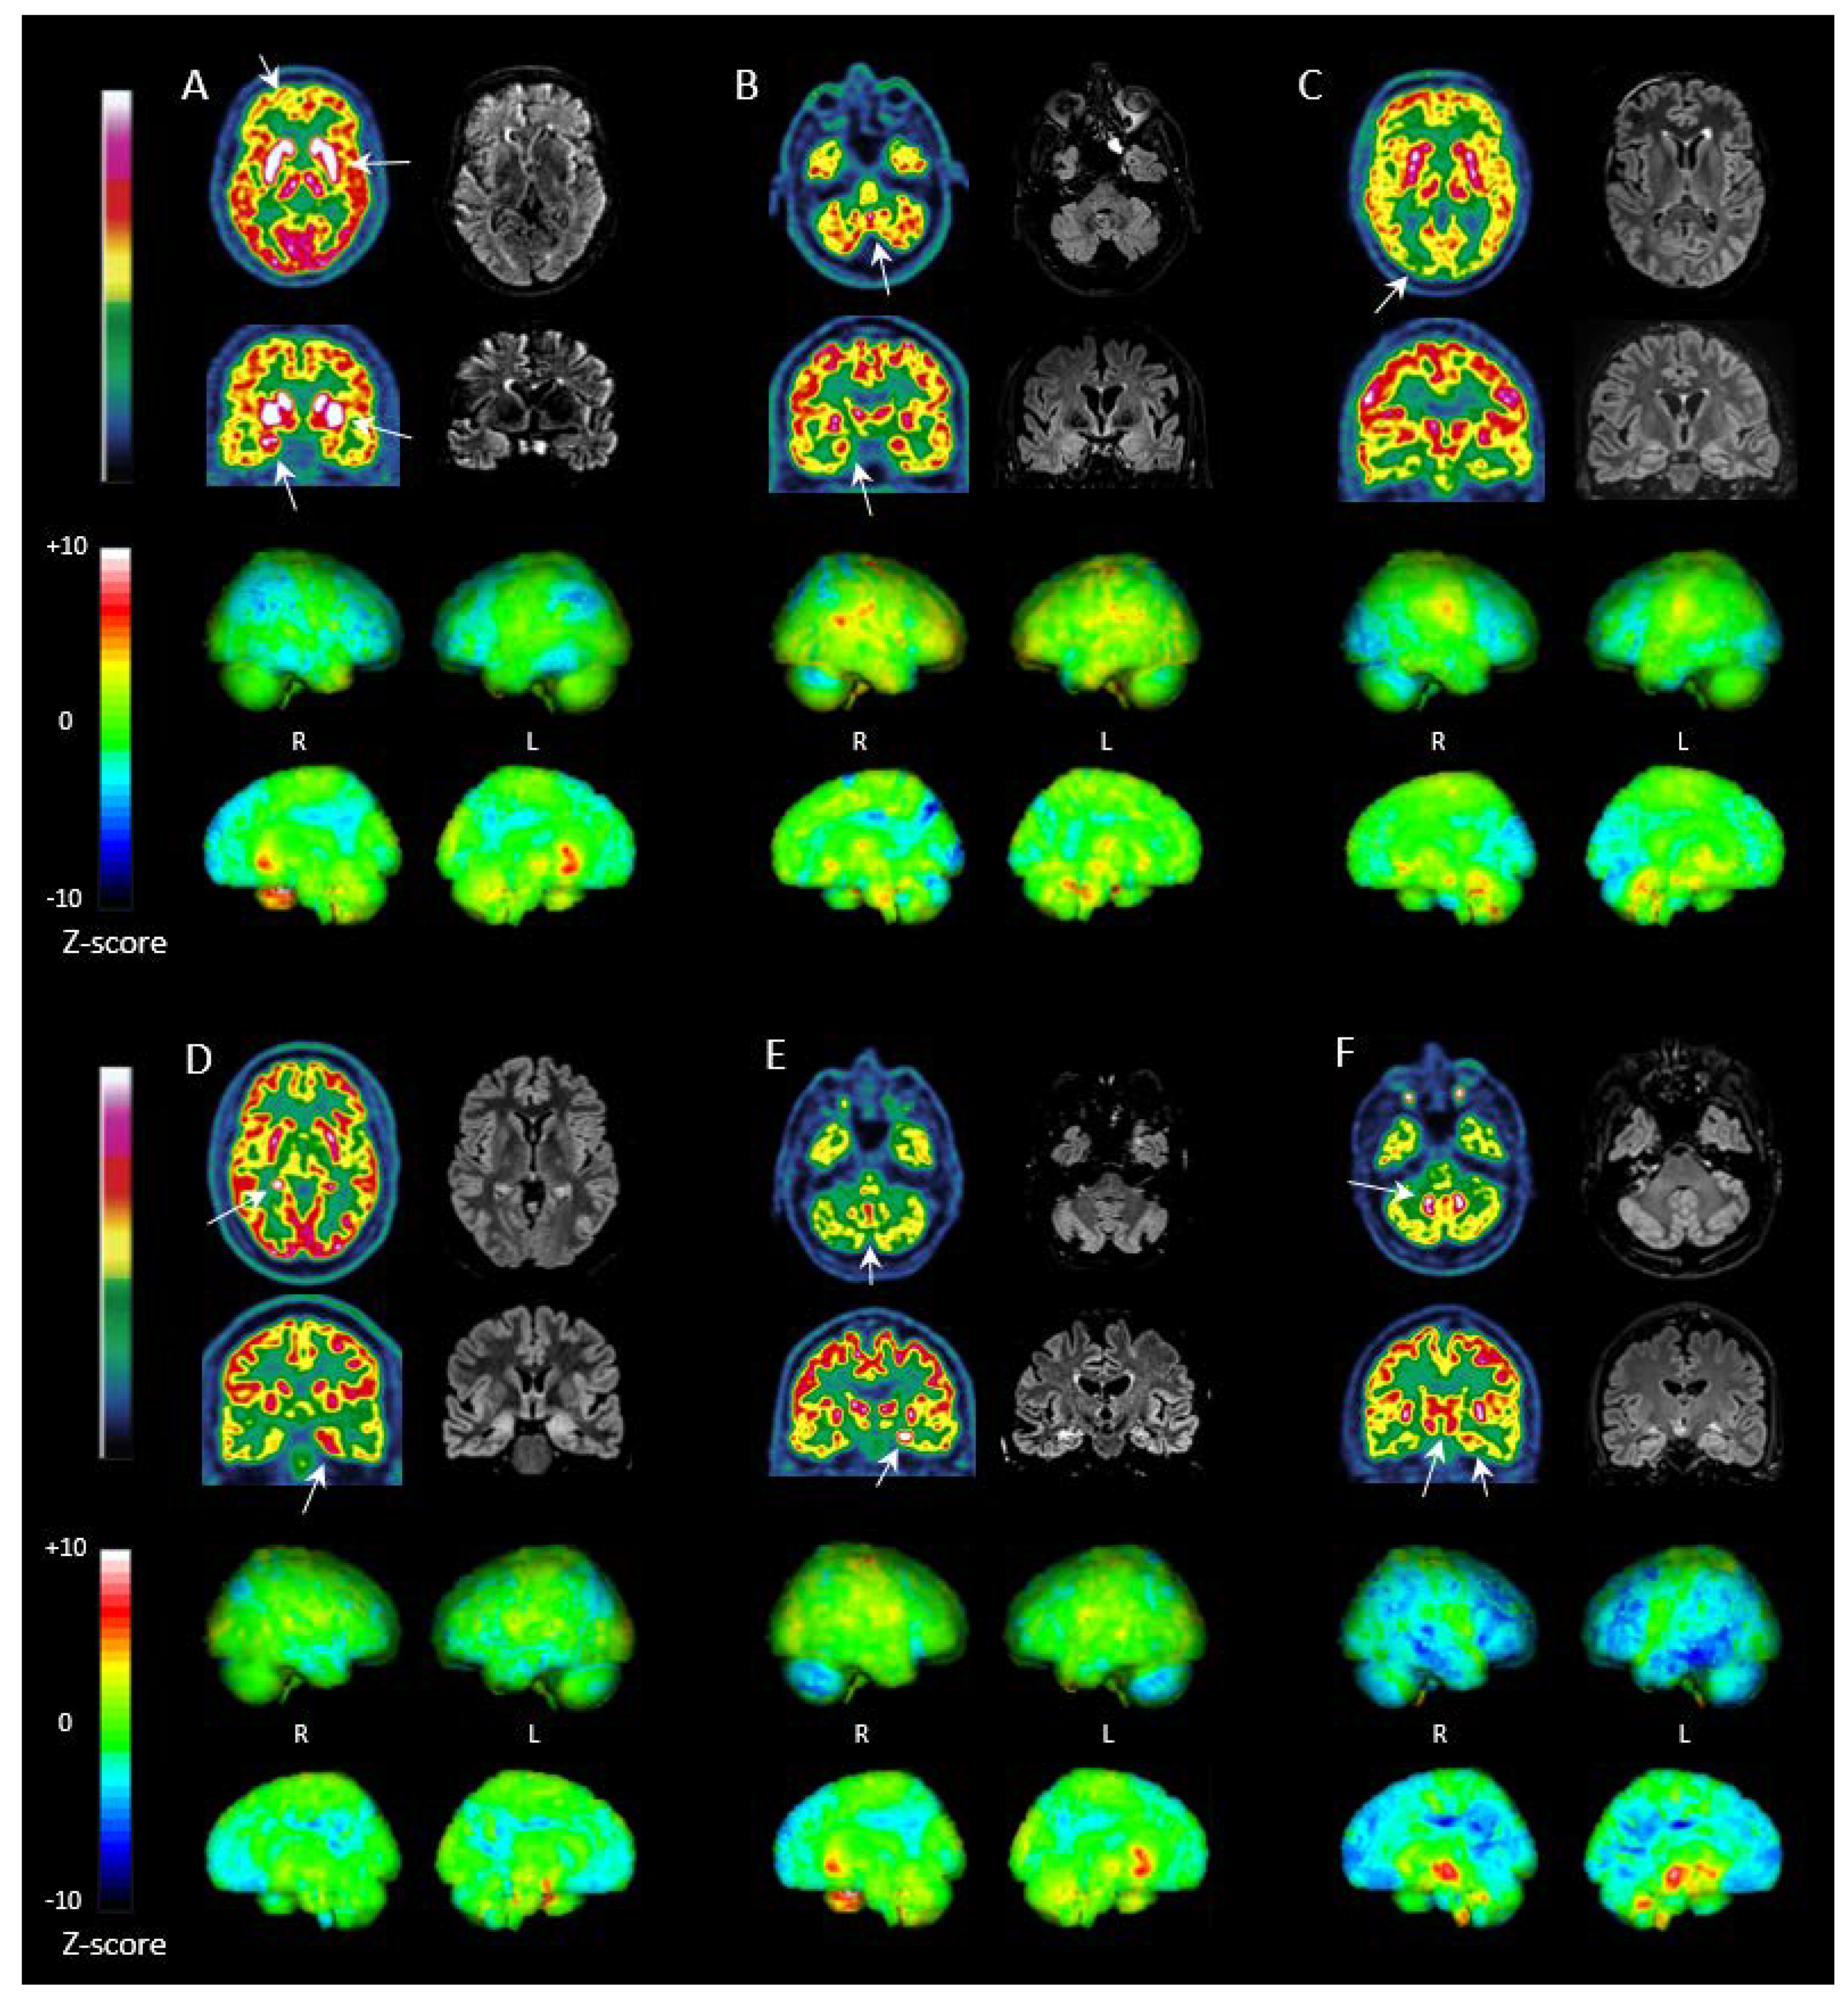

3.5. FDG PET in LGI1, NMDAR, GAD and CASPR2 Antibody Subtypes